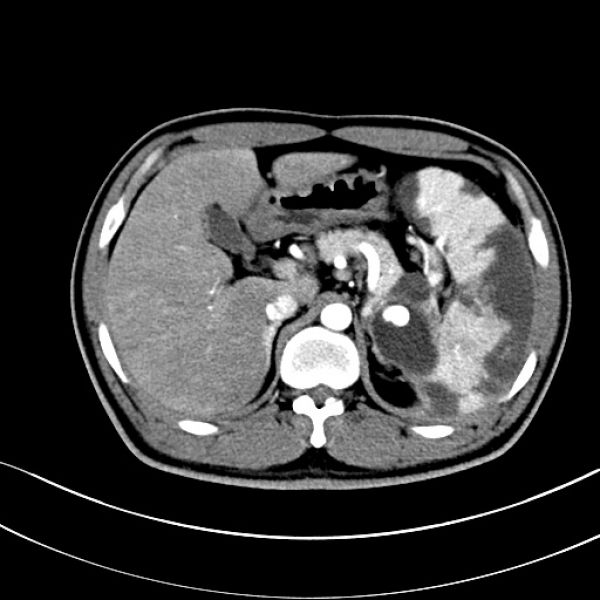

患者入院时CT提示:坏死性胰腺炎、合并假性囊肿形成、假性脾动脉瘤、左门脉高压症、脾梗死。病情紧急,且情况不容乐观。

时间就是生命,救治刻不容缓。肝胆外科一病区通过详细评估后,对病情的复杂性和术中风险有了充分准备。该患者集坏死性胰腺炎、合并假性囊肿形成、假性脾动脉瘤、左门脉高压症、脾梗死于一体,对医生的医术是一大考验,且术中极易发生大出血,不易控制。但胸有成竹的王文儿主任经过全科室术前讨论后,当即决定在患者入院的第二天进行急诊手术。历时4个多小时的生死赛跑,王文儿主任带领的肝胆外科一病区手术团队成功完成了这台“胰腺体尾部切除+胰腺假性囊肿剥除+脾脏切除术”的复杂急诊手术。术中仅出血300ml,术后患者恢复顺利,症状完全缓解,2周即康复出院。

术前CT